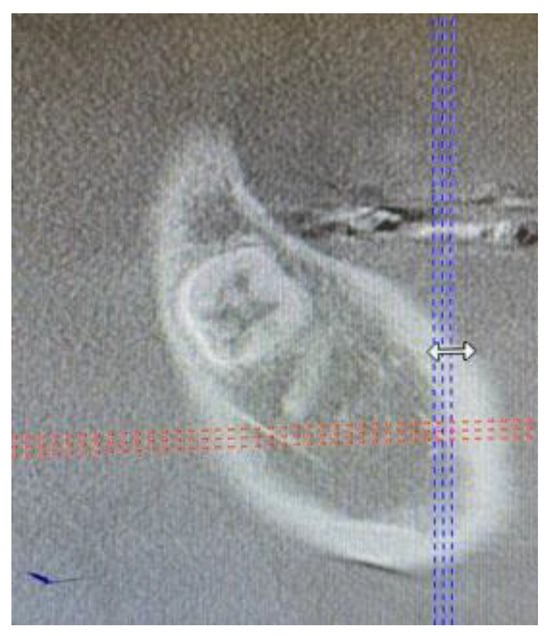

The patient was a generally healthy male without any history of surgery, illness, or surgery in the oral cavity region. The occurrence time of this lesion and its growth duration were not established. All of the surrounding anatomical areas and spaces were free of any diseases. Routine panoramic radiography (panx) and cone-beam computed tomography (CBCT) excluded any major changes in the bone near the tumour and excluded any potential odontogenic cause of the MRT swelling. The cortical parts of the bone in the CBCT study were also normal. No bone erosions, infiltrations, tooth resorptions, or bone swelling were detected (Figure 3). Because of the lack of substantial bone involvement, except for the impacted right mandibular wisdom molar with visible signs of bone ankylosis, suspicion of a nonodontogenic tumour was established.

Figure 3. Cone-beam computed tomography in the sagittal plane before biopsy. The superior part of the cortical bone remained clear and intact without any lesion or perforation.